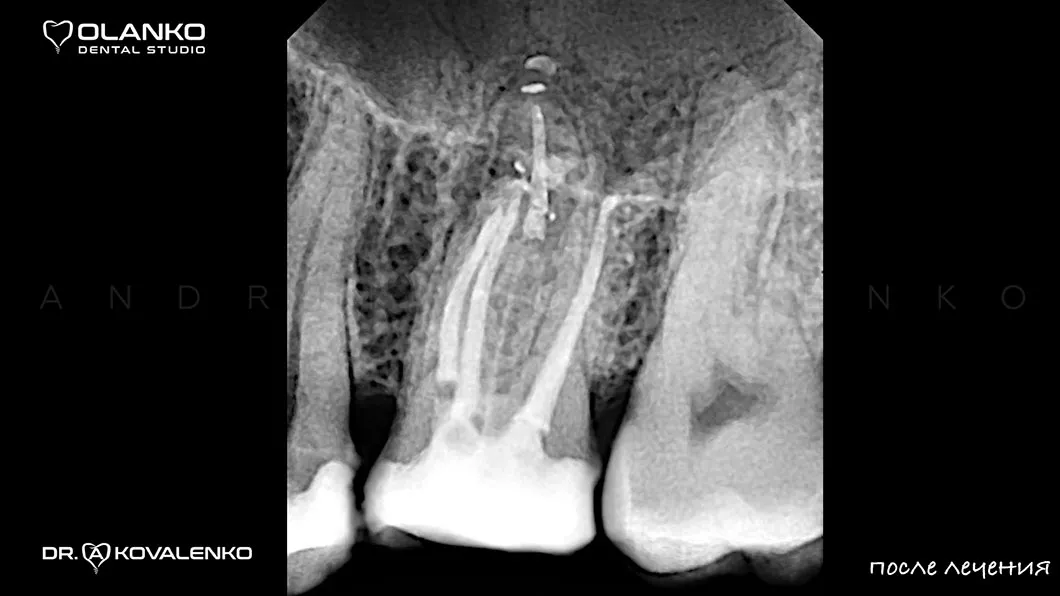

На примере перелечивания корневых каналов верхнего жевательного зуба

Мы имеем огромный клинический опыт лечения зубов со сложной анатомией (искривлёнными, склерозированными каналами), а также повторного перелечивания каналов с кистами, гранулемами, сломанными инструментами, с последующими отличными результатами заживления очагов хронического воспаления.